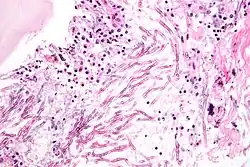

Cryptococcus

Cryptococcus neoformans can cause a severe form of meningitis and meningo-encephalitis in patients with HIV infection and AIDS. The majority of Cryptococcus species live in the soil and do not cause disease in humans. Cryptococcus neoformans is the major human and animal pathogen. Papiliotrema laurentii and Naganishia albida, both formerly referred to Cryptococcus, have been known to occasionally cause moderate-to-severe disease in human patients with compromised immunity. Cryptococcus gattii is endemic to tropical parts of the continent of Africa and Australia and can cause disease in non-immunocompromised people.[1]

Infecting C. neoformans cells are usually phagocytosed by alveolar macrophages in the lung.[11] The invading C. neoformans cells may be killed by the release of oxidative and nitrosative molecules by these macrophages.[12] However some C. neoformans cells may survive within the macrophages.[11] The ability of the pathogen to survive within the macrophages probably determines latency of the disease, dissemination and resistance to antifungal agents. In order to survive in the hostile intracellular environment of the macrophage, one of the responses of C. neoformans is to upregulate genes employed in responses to oxidative stress.[11]